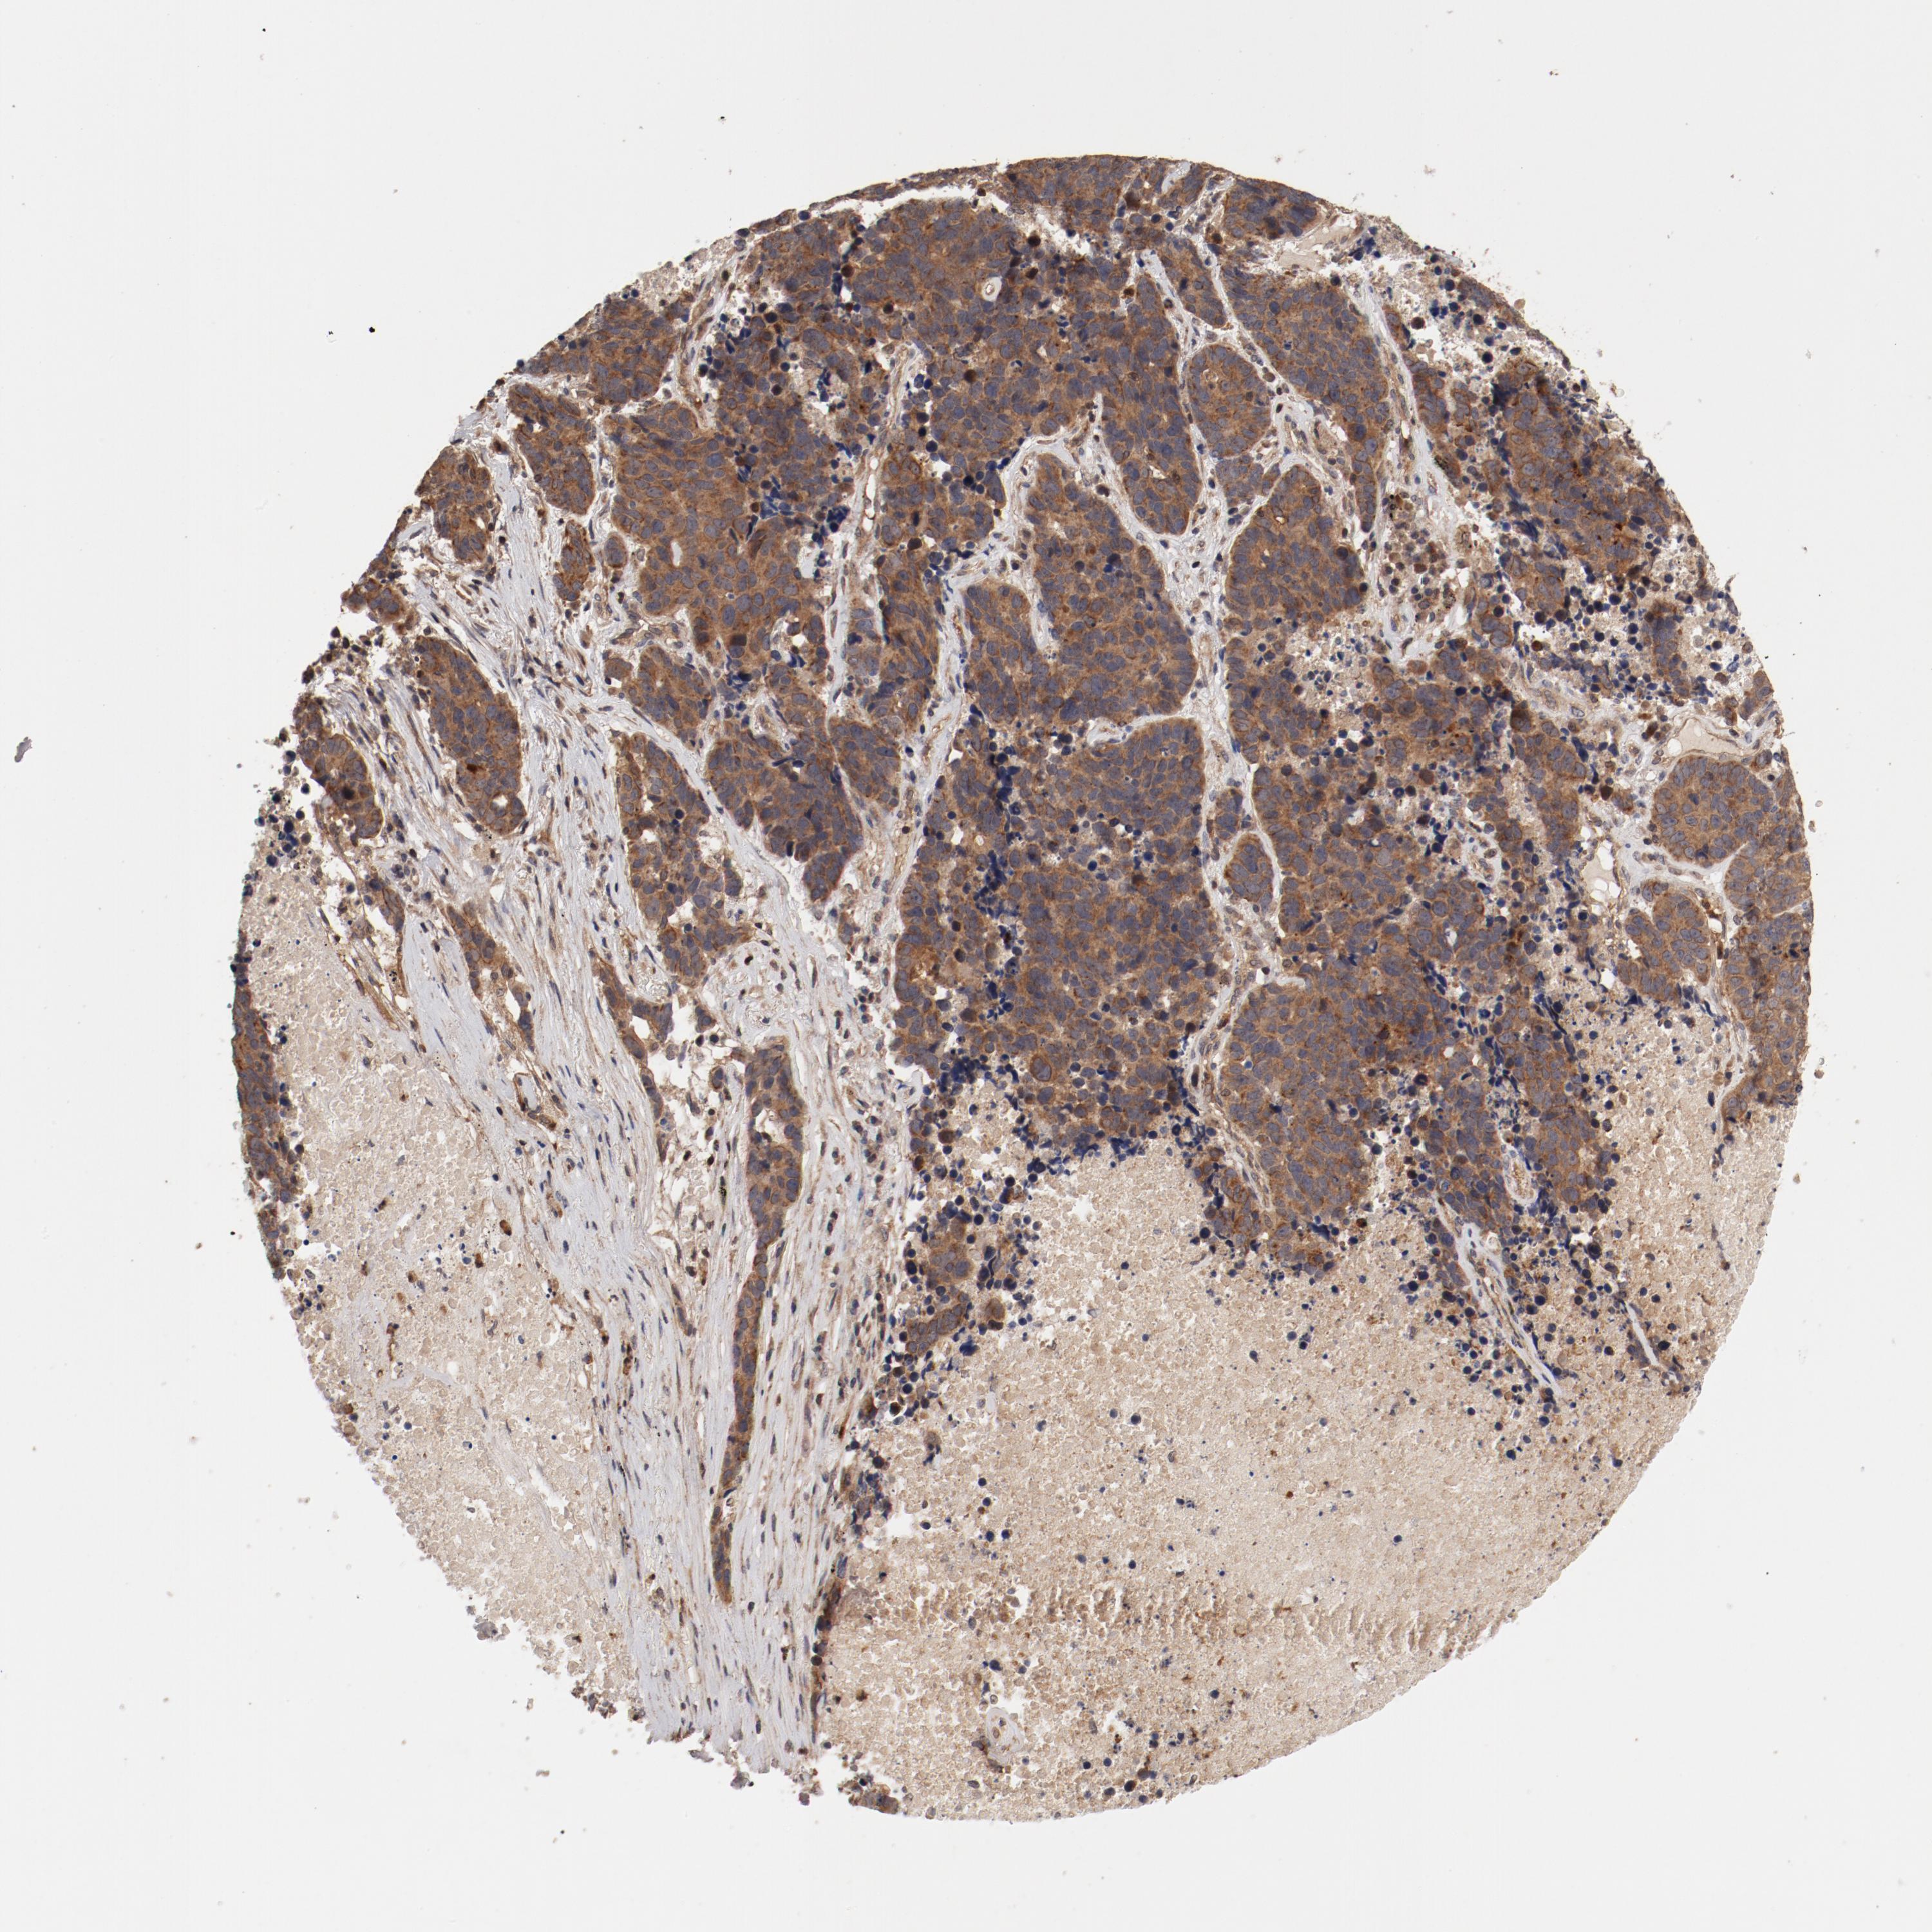

LUNG SQUAMOUS CELL CARCINOMA (TCGA) - Interactive survival scatter ploti

The Survival Scatter plot shows the clinical status (i.e. dead or alive) for all individuals in the patient cohort, based on the same data that underlies the corresponding Kaplan-Meier plots. Patients that are alive at last time for follow-up are shown in blue and patients who have died during the study are shown in red.

The x-axis shows the expression levels (FPKM) of the investigated gene in the tumor tissue at the time of diagnosis. The y-axis shows the follow-up time after diagnosis (years). Both axes are complimented with kernel density curves demonstrating the data density over the axes. The top density plot shows the expression levels (FPKM) distribution among dead (red) and alive patients (blue). The right density plot shows the data density of the survived years of dead patients with high and low expression levels respectively, stratified using the cutoff indicated by the vertical dashed line through the Survival Scatter plot. This cutoff is automatically defined based on the FPKM cutoff that minimizes the p-score. The cutoff can be changed by dragging the vertical line or by entering a cutoff value in the square labeled "Current cut-off".

Under the Survival Scatter plot the p-score landscape (black curve; left axis) is shown together with dead median separation (red curve; right axis). Dead median separation is the difference in median mRNA expression between patients who have died with high and low expression, respectively. It is calculated as follows: median FPKM expression of dead patients with high expression - median FPKM expression of dead patients with low expression. This is intended to aid the user in visually exploring custom cutoffs and the associated p-scores and dead median separation.

Individual patient data is displayed and can be filtered by clicking on one or more of the category buttons on the top of the page. Categories describing expression level and patient information include: high, low, alive, dead, female, male and tumor stages. The scale of the x-axis can be toggled between linear and log-scale by clicking on the "x log" button. Mouse-over function shows TCGA ID, patient information and mRNA expression (FPKM) for each patient.

& Survival analysisi

Kaplan-Meier plots summarize results from analysis of correlation between mRNA expression level and patient survival. Patients were divided based on level of expression into one of the two groups "low" (under cut off) or "high" (over cut off). X-axis shows time for survival (years) and y-axis shows the probability of survival, where 1.0 corresponds to 100 percent.

GUF1 is not prognostic in Lung Squamous Cell Carcinoma (TCGA)

: 2.17